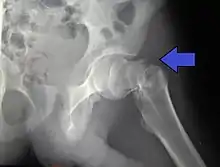

Intertrochanteric hip fracture in a 17-year-old male

Fracture (black arrow, pertrochanteric) versus a skin fold (white arrow).